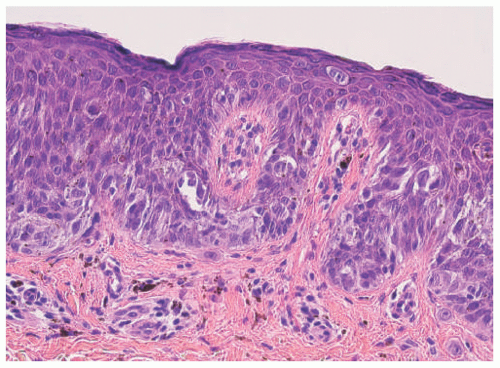

DN is defined as a melanocytic lesion without a junctional component. It is often characterized as a soft dome-shaped lesion whose differential diagnosis may include neurofibroma. Both the compound nevus and DN may be associated with alterations in the overlying epidermis including marked acanthosis or seborrheic keratosis-like architecture. With the loss of the junctional component, DN often appears lighter in color. Although we generally do not divide DN into the so-called Unna and Miescher patterns, the former is recognized by a widened papillary dermis, whereas the latter has a more diffuse infiltrative growth into the reticular dermis (Figure 22-8A-C).30 Those DNs with the diffuse pattern can have a prominent fibrillary matrix or stroma and tactile body-like formations that have been referred to as neurotization with a resemblance to a neurofibroma. Adipose tissue and heterotopic bone (osteonevus of nanta) are other less common findings whose presence reflects the range of mesenchymal differentiation in NC-derived proliferations. Though uncommon in DNs from children, so-called ancient changes can be mistaken for melanoma.31 Exclusively dermal-based melanocytic nevi are seen in several other specific contexts including the SN, DPN, BN, and CMN.

FIGURE 22-8. A, Dermal melanocytic nevus from the trunk of a 17-year-old female. Note the alterations of the overlying epidermis and the expansion of the papillary dermis. B, The nevus cells even in this obviously benign lesion show variations of cell size and scattered dense nuclei that may represent pyknosis rather than atypia. C, Nuclear pseudoinclusions and multinucleated nevus cells are present in this field.